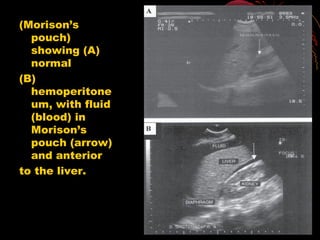

(A) normal

image, and

(B) image

positive

for fluid

(blood) in

the

spleno-

renal

recess.

(A) normal image, and (B)image positive for fluid (blood) in the spleno- renal recess.